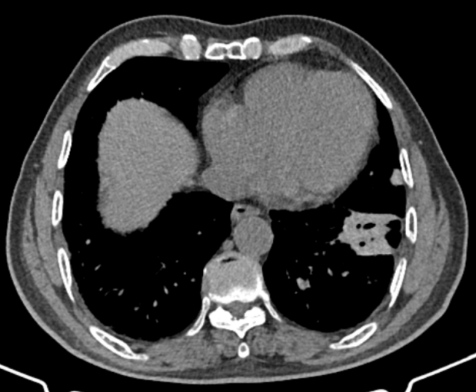

此次手术患者是喀什地区第一人民医院的一名55岁病人,因“间断咳嗽、咳痰、气短2年,再发5天”入院,术前CT显示“左下叶前内基底段囊实性病灶,边缘不规整,内部多发囊状影,约30*27mm”。(图1)

喀什地区第一人民医院的一名55岁病人术前CT(图1)